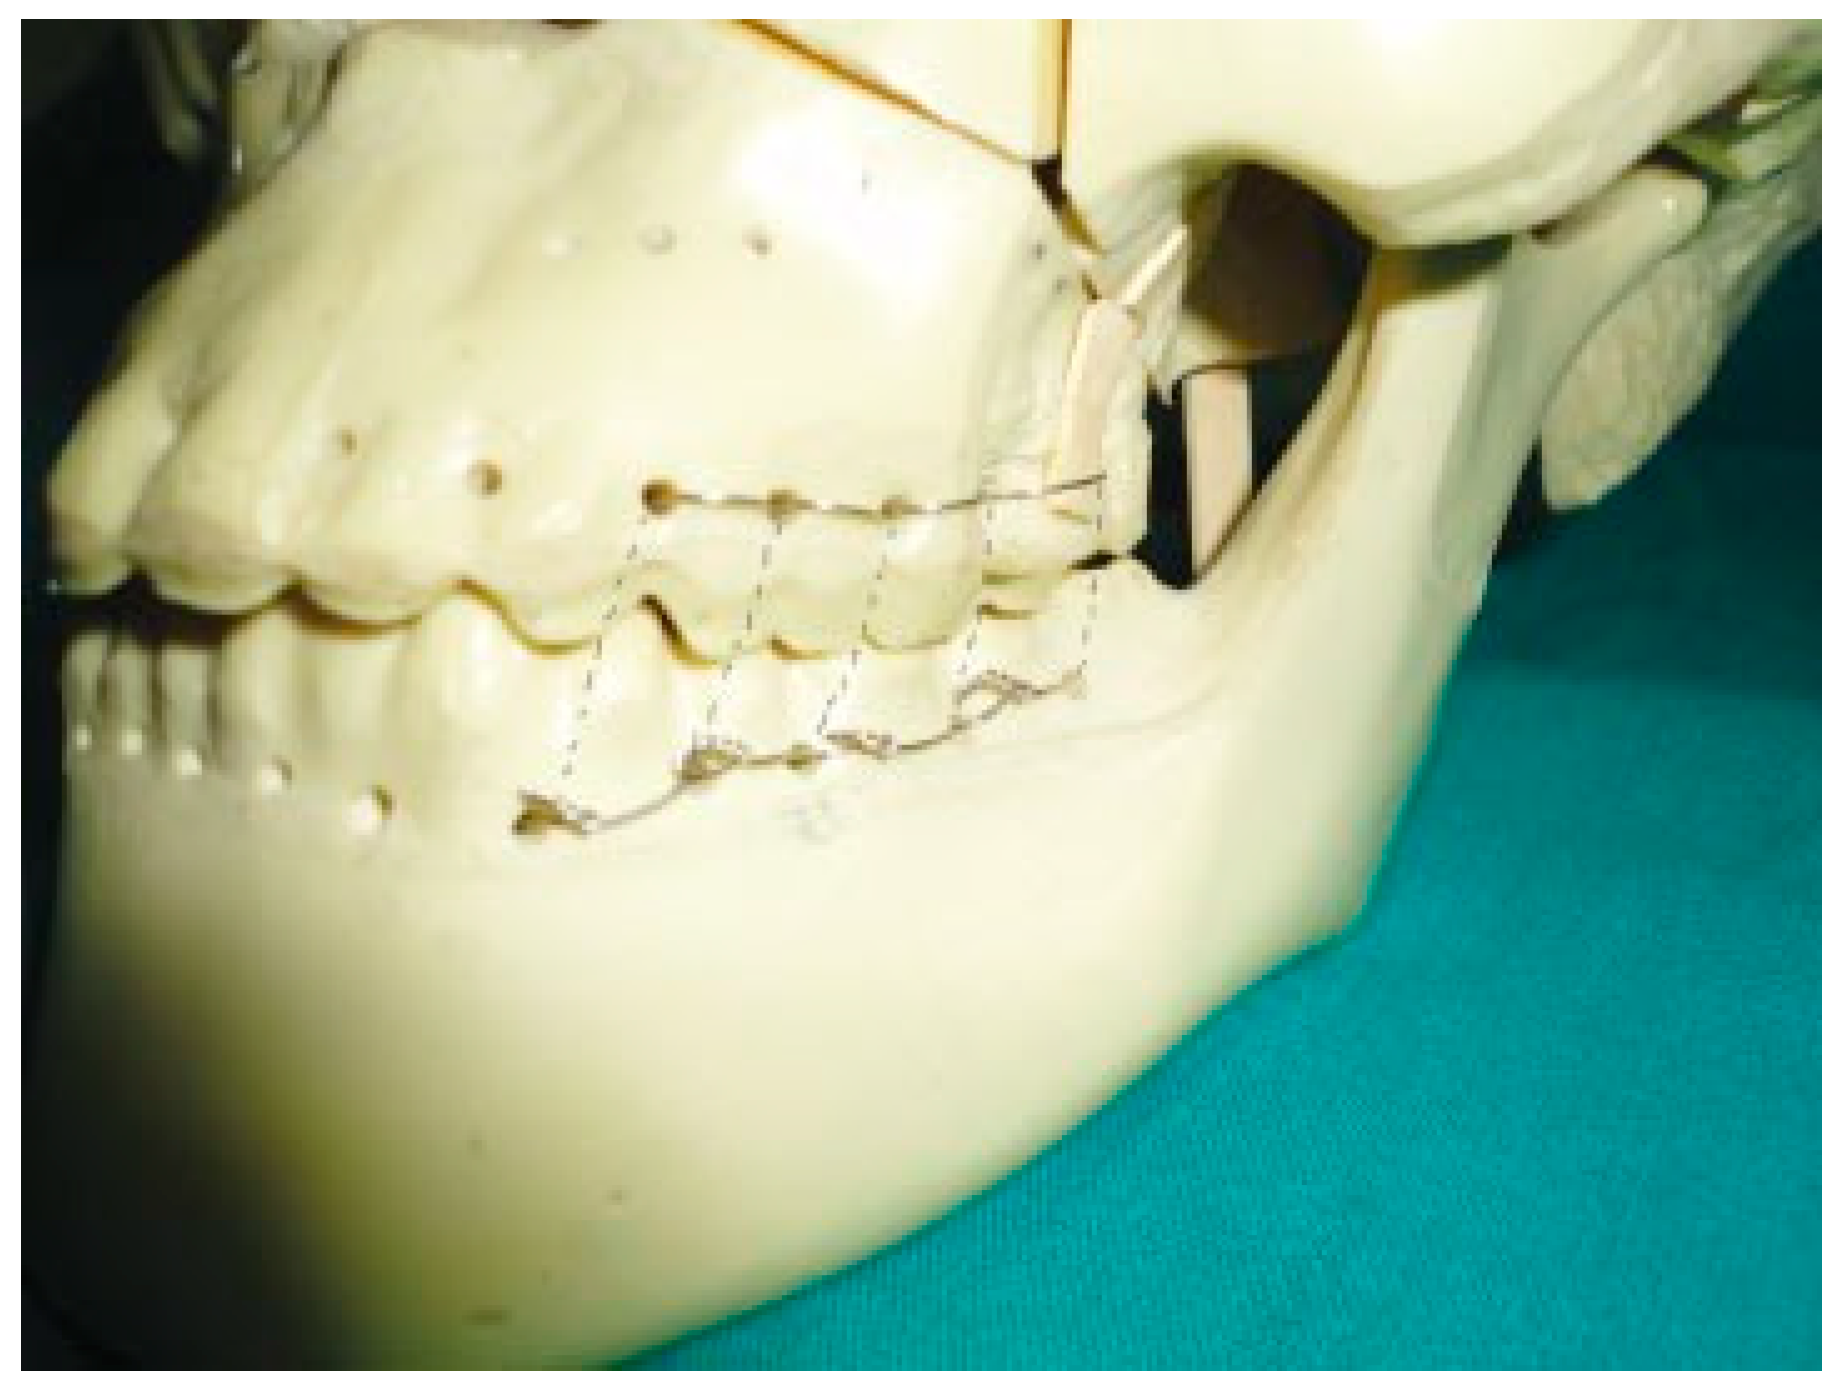

Figure 2. Step 1 of the technique.

In this technique, a wire is passed around the neck of the upper first molar tooth; both ends of the wire go from buccal to palatal, one along the mesial surface and other end along the distal surface of tooth above the maxillary contact (Figure 2). Then both ends of the wire are passed back around the lower first molar from lingual to buccal aspect in a similar manner below the mandibular contact (Figure 3). A similar procedure is repeated on the second molar and premolar teeth and on the contralateral side (molar and premolar region). After achieving the occlusion, the ends of the wire are twisted together on the buccal surface of the lower premolar and molar teeth on both sides (Figure 4, Figure 5 and Figure 6). At the end of treatment, wires can be easily removed with minimal trauma to patient.